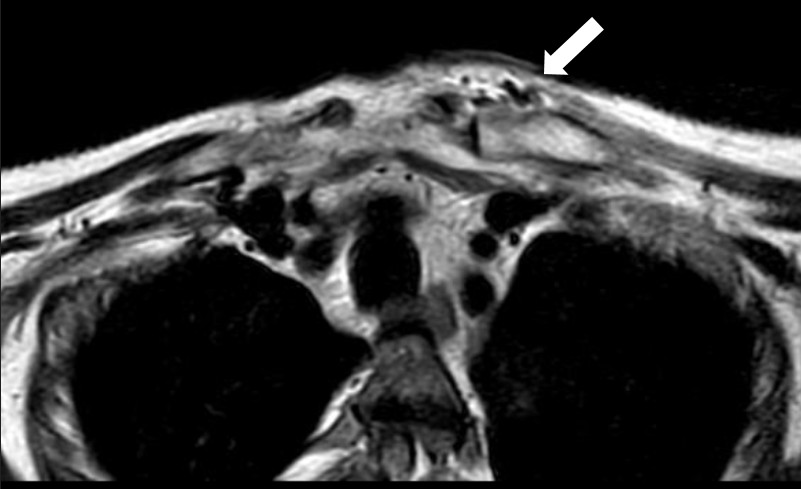

MRI of the chest showed findings consistent with osteomyelitis, including bone irregularities, edema, subchondral erosions of the right sternoclavicular joint, synovitis, and inflammatory joint changes (Fig. 2- 4).

Figure 3. Axial magnetic resonance imaging. Lytic lesion with periosteal reaction characteristic of osteomyelitis.

Figure 4. Coronal magnetic resonance imaging ESAG T2. Osteolytic lesion in sternal profile with periosteal reaction of the manubrio.